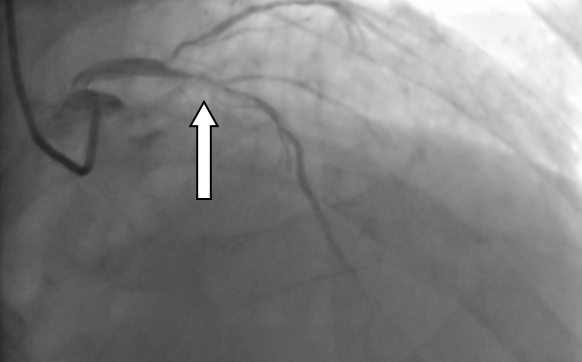

▲冠状动脉内膜旋磨术进行中。 通俗说钙化:血管里的“水垢”是什么? 提到冠心病,大家并不陌生,但冠脉钙化是什么?简单来说,就像家里用了几十年的水管,内壁会慢慢结满厚厚的水垢,血管也会因年龄增长、代谢变化,在血管壁上形成坚硬的钙化斑块——这种斑块质地坚硬,会不断变厚、缩小血管管腔,导致心脏供血不足,严重时会引发胸痛、心肌缺血,甚至危及生命,对高龄老人来说,风险更为突出。 九旬老人的难题:血管堵得只剩细缝 冯伯的案例就是典型的高危冠脉钙化情况。他因反复胸痛就医,冠脉造影检查发现,心脏三支主要供血血管均出现病变,其中最关键的供血血管——左前降支,近中段布满了厚厚的钙化斑块,血管狭窄程度高达95%,心脏供血已严重受限。更关键的是,93岁的高龄让他的血管变得壁厚、质硬、弹性差,形成了“高阻力钙化病变”,给治疗带来了极大难度。 ▲造影显示患者血管血管狭窄程度高达95%。 很多人会问,普通的心脏介入手术不能解决吗?我院心血管内科一区专家解释:“严重钙化的血管就像结满厚水垢的老旧水管,僵硬又狭窄,常规的球囊扩张术,就像用气球去吹硬邦邦的水管,根本无法将钙化斑块撑开,强行操作还可能导致血管撕裂、损伤,反而增加风险。” 对付硬钙化:“金刚钻”来帮忙 面对这种高难度的钙化病变,冠状动脉内膜旋磨术就成了针对性的治疗方式。针对冯伯的病情,医疗团队经反复评估后,决定采用这项技术为他治疗,而这项技术,也是目前应对坚硬冠脉钙化的常用微创手段之一。 冠状动脉内膜旋磨术的原理并不复杂,核心就是用“金刚钻”样的工具,精准磨掉血管内的坚硬钙化斑块。手术时,医护人员会通过微创方式,将一根顶端镶有微小钻石颗粒的橄榄型旋磨头,送入堵塞的血管内,让旋磨头以极高的速度旋转,将坚硬的钙化斑块研磨成直径小于5微米的微小微粒——这种微粒比红细胞还要小,会随着血液循环被人体自身的吞噬细胞清除,不会对身体造成额外伤害,从而打通堵塞的血管通路。 虽然原理简单,但这项手术对操作精度要求极高:既要彻底磨碎钙化斑块,打通血管通路,又要小心翼翼保护血管内壁,避免造成血管损伤。手术中,医疗团队全程精准操控旋磨头,顺利完成旋磨术后,又通过植入药物洗脱支架,进一步巩固治疗效果,防止血管再次狭窄。 术后恢复:老人终于不胸痛了 术后复查结果显示,支架贴合良好,原本严重堵塞的血管恢复了通畅,冯伯的胸痛症状缓解,心脏供血恢复正常,精神状态也日渐好转,最终顺利康复出院。 ▲支架植入术后,冠脉恢复正常供血。 结合这个案例,我们可以了解到一个重要的知识点:高龄并非复杂冠脉钙化介入治疗的绝对禁区。我院心血管内科一区主任医师陈文广表示,这类手术的成功,离不开术前精准的病情评估、术中娴熟的操作技巧以及多学科的密切配合,而这也为高龄冠脉钙化患者的治疗提供了可行的思路——经严格评估后,合适的微创技术可以有效解决这类心脏难题。 温馨提示: 正视血管钙化,及时就医 随着人口老龄化加剧,高龄、高危冠脉钙化患者越来越多,也让这类心脏问题受到更多关注。冠状动脉内膜旋磨术等微创技术的应用,不仅为这类患者提供了更多治疗选择,也让我们意识到,科学认识冠脉钙化、及时规范就医,才能更好地守护老年人群的“心”健康。 心血管内科一区简介 基本概况 我院心血管内科一区现有医护人员32名,开放床位46张,其中重症监护室(CCU)床位14张。科室配备数字减影血管造影机、血管内超声仪、血管内旋磨仪、主动脉内球囊反搏仪、心排血量监测仪等专业医疗设备,为临床诊疗工作提供硬件支持。 诊疗技术 科室在冠心病、心力衰竭、心律失常、主动脉夹层、心脏瓣膜病、心肌病、外周血管闭塞性疾病等心血管疾病的诊疗方面积累了丰富经验,针对急性心肌梗死、心源性休克、急慢性心力衰竭、主动脉夹层或动脉瘤、严重心律失常等急危重症病例,开展规范的诊断与救治工作。 临床工作中,科室常规开展心血管介入检查及治疗项目,包括冠脉支架植入术、冠脉血管内旋磨术、心脏射频消融术、主动脉腔内隔绝术、永久起搏器植入术、下腔静脉滤器植入术、肾动脉支架植入术、下肢动脉支架植入术等。 科室曾在“县域中国医院品牌专科评选”中获评第二名,先后获得“阳江市青年文明号”称号,连续多年被评为医院先进科室,团队始终秉持严谨务实的工作作风,为患者提供专业的医疗服务。 专家简介 陈文广 心血管内科主任医师,心血管内科一区主任、教授,心血管介入学科带头人、胸痛中心医疗总监。 担任广东省医师协会心脏病器械辅助治疗医师分会第三届委员会常务委员、广东省医师协会心血管内科医师分会第四届委员会委员、广东省卫生经济学会心血管疾病分会常务委员、广东省中医药学会心力衰竭专业委员会第二届常务委员、广东省基层医药学会中西医结合心血管专业委员会第二届常务委员、广东省中西医结合学会心血管介入专业委员会委员、广东省中医药学会心脏血脉专业委员会委员、广东省医师协会心脏起搏与电生理专医师分会第二届委员会基层医院心脏起搏与电生理专业组成员,阳江市医学会心脏介入分会第二届委员会副主任委员、,阳江市医学会心血管内科分会第二届委员会副主任委员、阳江市医师协会心内科医师分会第二届委员会副主任委员等。参与国家级临床科研项目1项,省级及市级临床科研项目多项;撰写著作多本,发表10多篇省级以上论文。 擅长领域:从事心血管疾病介入治疗10多年,累计有5000多例冠状动脉支架植入术(PCI)的手术经验。擅长冠心病、高血压、心衰、主动脉夹层、心脏瓣膜病、心律失常等心血管疾病的诊治,熟练掌握冠心病、左主干病变、多支血管病变、高危病变、钙化、分叉、慢性闭塞病变、临时及永久起搏器植入、主动脉覆膜支架腔内隔绝术、下腔静脉滤器植入、外周血管介入治疗等介入技术治疗。 崔 跃 心血管内科副主任医师,心血管内科一区副主任。 广东省医师协会高血压分会委员、阳江市医学会心血管分会常务委员、阳江市医学会心脏介入分会常务委员、阳江市医师分会心血管分会常务委员。参与国家级临床科研项目1项,市级临床科研项目3项;撰写著作1本,发表6多篇省级以上论文。曾多次到上级医院心血管内科进修学习,其中到中山大学第一附属医院进修心血管重症班,另先后三次到南方医院附属珠江医院进修学习心血管介入技术。 擅长领域:熟练掌握心血管介入技术,独立完成冠状动脉造影手术和冠状动脉介入手术,擅长心肌梗死、恶性心律失常、急重症心衰等的抢救。 黄 毅 心血管内科副主任医师,介入科副主任,胸痛中心秘书及协调员。 广东省胸痛中心协会委员、广东省介入学会结构性心脏病分会委员、广东省健康管理学会肺血管病专业委员会委员、阳江市医学会心血管内科分会常务委员、阳江市医学会心脏介入分会常务委员、阳江市医师协会心内科医师分会委员,阳江市医学会心脑同治分会常务委员。主持阳江市卫生健康局科技研究立项1项,主持阳江市科学技术局科技研究立项3项,参与阳江市科学技术局科技研究多项。主编《高血压及相关疾病现代诊疗》,发表国家级专业论文4篇、省级专业论文2篇。2010年毕业于广东医科大学临床医学专业,毕业后一直从事心血管内科工作,曾先后到南方医科大学珠江医院进修学习冠心病介入技术(PCI)和广东省人民医院心研所(国家班)进修结构性心脏病(包括先天性心脏病介入封堵、左心耳封堵、二尖瓣狭窄球囊扩张、肺血管病介入等)。 擅长领域:主要致力于冠心病介入、结构性心脏病介入(包括先天性心脏病介入封堵、左心耳封堵、二尖瓣狭窄球囊扩张、肺血管病介入等)、B型主动脉夹层介入、下肢动脉闭塞介入、高血压、急慢性心力衰竭、肺动脉高压的诊断与治疗。 许军国 普通内科副主任医师。 阳江市医学会心血管分会委员、阳江市医师分会心血管分会委员。1996年广东医学院临床医学毕业。曾到暨南大学第一附属医院进修重症医学科,2020年在中山大学附属第一医院进修心血管重症科CCU。 擅长领域:从事心血管疾病诊治工作25年,擅长心血管疾病重症治疗,在冠心病心肌梗死、高血压、心律失常、心力衰竭等疾病治疗上有丰富临床经验。 李昌利 心血管内科副主任医师。 阳江市医学会脑心同治分会第二届委员会常务委员、阳江市医学会心血管内科分会委员、阳江市医学会心脏介入分会委员、阳江市医师协会心内科医师分会委员。毕业于广东医学院(今广东医科大学),毕业后在阳春市人民医院工作至今。 擅长领域:擅长治疗高血压病、冠心病、心力衰竭、房颤、下肢静脉血栓等心血管疾病。 张智华 心血管内科副主任医师。 阳江市医学会脑心同治分会第二届委员会常务委员、阳江市医学会心血管内科分会委员、阳江市医学会心脏介入分会委员、阳江市医师协会心内科医师分会委员。毕业于广东医科大学临床医学专业,2016年到南方医科大学珠江医院进修学习冠心病介入技术。2021年在中山大学附属第一医院进修心血管内科。 擅长领域:擅长冠心病、高血压、心力衰竭、心律失常的诊断与治疗,熟练掌握冠状动脉介入操作及冠状动脉介入治疗技术。 滕 超 心血管内科主治医师。 阳江市医学会脑心同治分会第二届委员会常务委员、阳江市医学会心血管内科分会委员、阳江市医学会心脏介入分会委员、阳江市医师协会心内科医师分会委员。毕业于广西中医药大学,2019年到广东省人民医院进修学习冠心病介入技术。 擅长领域:擅长冠心病、高血压病、心力衰竭、下肢深静脉血栓形成等疾病的诊治。熟练掌握冠状动脉造影及冠状动脉介入治疗技术。 莫介超 心血管内科主治医师。 阳江市医学会脑心同治分会第二届委员会常务委员、阳江市医学会心血管内科分会委员、阳江市医学会心脏介入分会委员、阳江市医师协会心内科医师分会委员。毕业于广东医科大学临床医学专业,2016年到南方医科大学珠江医院进修学习心血管内科,2023年到中山医科大学附属第一医院进修心律失常介入技术。 擅长领域:擅长心律失常、冠心病、心力衰竭、高血压等疾病的诊断与治疗。 刘艺豪 心血管内科主治医师。 阳江市医学会脑心同治分会第二届委员会常务委员、阳江市医学会心血管内科分会委员、阳江市医学会心脏介入分会委员、阳江市医师协会心内科医师分会委员。毕业于广东医科大学临床医学专业,2020年在中山医科大学第一附属医院进修心血管内科。 擅长领域:从事心血管疾病诊治多年,擅长高血压病、急性心肌梗死、冠心病、心肌病、心律失常等疾病以及各种心脏急症、内科危重症的救治。 张杰亮 心血管内科主治医师。 阳江市医学会脑心同治分会第二届委员会常务委员、阳江市医学会心血管内科分会委员、阳江市医学会心脏介入分会委员、阳江市医师协会心内科医师分会委员。2015毕业于广东医科大学临床医学专业,2020年完成全国内科规范化培训。 擅长领域:擅长冠心病、高血压病、心力衰竭、急性心肌梗死、心律失常等疾病以及各种心脏急症、危重症的救治。 蓝昭海 心血管内科主治医师 2017年毕业于汕头大学临床医学专业,2021年完成全国住院医师规范化培训。 擅长领域:擅长冠心病、高血压病、心力衰竭、急性心肌梗死、心律失常等疾病以及各种心脏急症、危重症的救治。